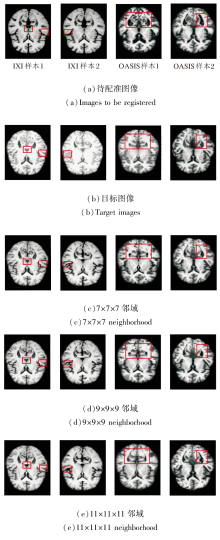

基于局部邻域内的像素强度统计相关性计算相似性损失函数, 邻域尺寸直接影响度量的鲁棒性.尺寸过小会导致局部采样不足, 难以捕捉完整的解剖强度分布, 降低对结构细节的敏感性; 尺寸过大容易引入无关区域的强度干扰, 模糊局部对应关系.为此, 本文设置7× 7× 7、9× 9× 9、11× 11× 11的邻域尺寸.

在IXI、OASIS数据集上各自选取2个样本, 邻域尺寸改变后图像配准结果如图19所示, 对PyraMLP-Net性能的影响如图20所示.

由图19和图20可见, 9× 9× 9邻域尺寸在DSC、HD95指标上均取得最优值.在IXI数据集上, 相比7× 7× 7邻域和11× 11× 11邻域, 9× 9× 9邻域的DSC值分别提高约0.6%和1.2%, HD95值分别降低约2.2%和8.3%.

在OASIS数据集上, 相比7× 7× 7邻域和11× 11× 11邻域, 9× 9× 9邻域的DSC值分别提高约0.7%和1.3%, HD95值分别下降约5.4%和9.5%.

性能差异源于不同邻域尺寸对图像噪声、解剖结构覆盖和相似性度量可靠性的影响.7× 7× 7邻域涵盖体素数量有限, 局部灰度均值容易受到图像噪声和伪影干扰, 降低相似性损失的稳定性, 从而影响配准精度.11× 11× 11邻域由于覆盖范围过大, 可能引入不相关解剖结构的干扰, 导致图像相似性度量无法准确反映目标解剖对应关系, 同样限制配准性能.相比之下, 9× 9× 9邻域在局部细节保留与噪声鲁棒性之间实现良好平衡, 既能抑制噪声敏感问题, 也能避免大邻域带来的结构混淆问题, 有效提高配准精度.